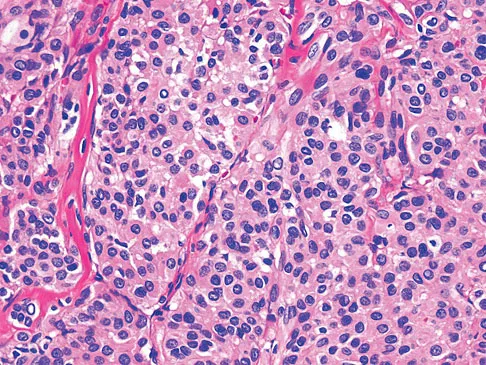

A 69-year-old woman reports a painful clicking in her right shoulder. A soft-tissue mass is palpated at the lower portion of the scapula. Based on the MRI scan and biopsy specimens shown in Figures 72a through 72c, what is the most likely diagnosis?

Question 18

A 10-month-old boy has multiple skeletal lesions and a skin rash that he has had since he was a newborn. Based on the radiographs and biopsy specimens shown in Figures 79a through 79d, what is the most likely diagnosis?